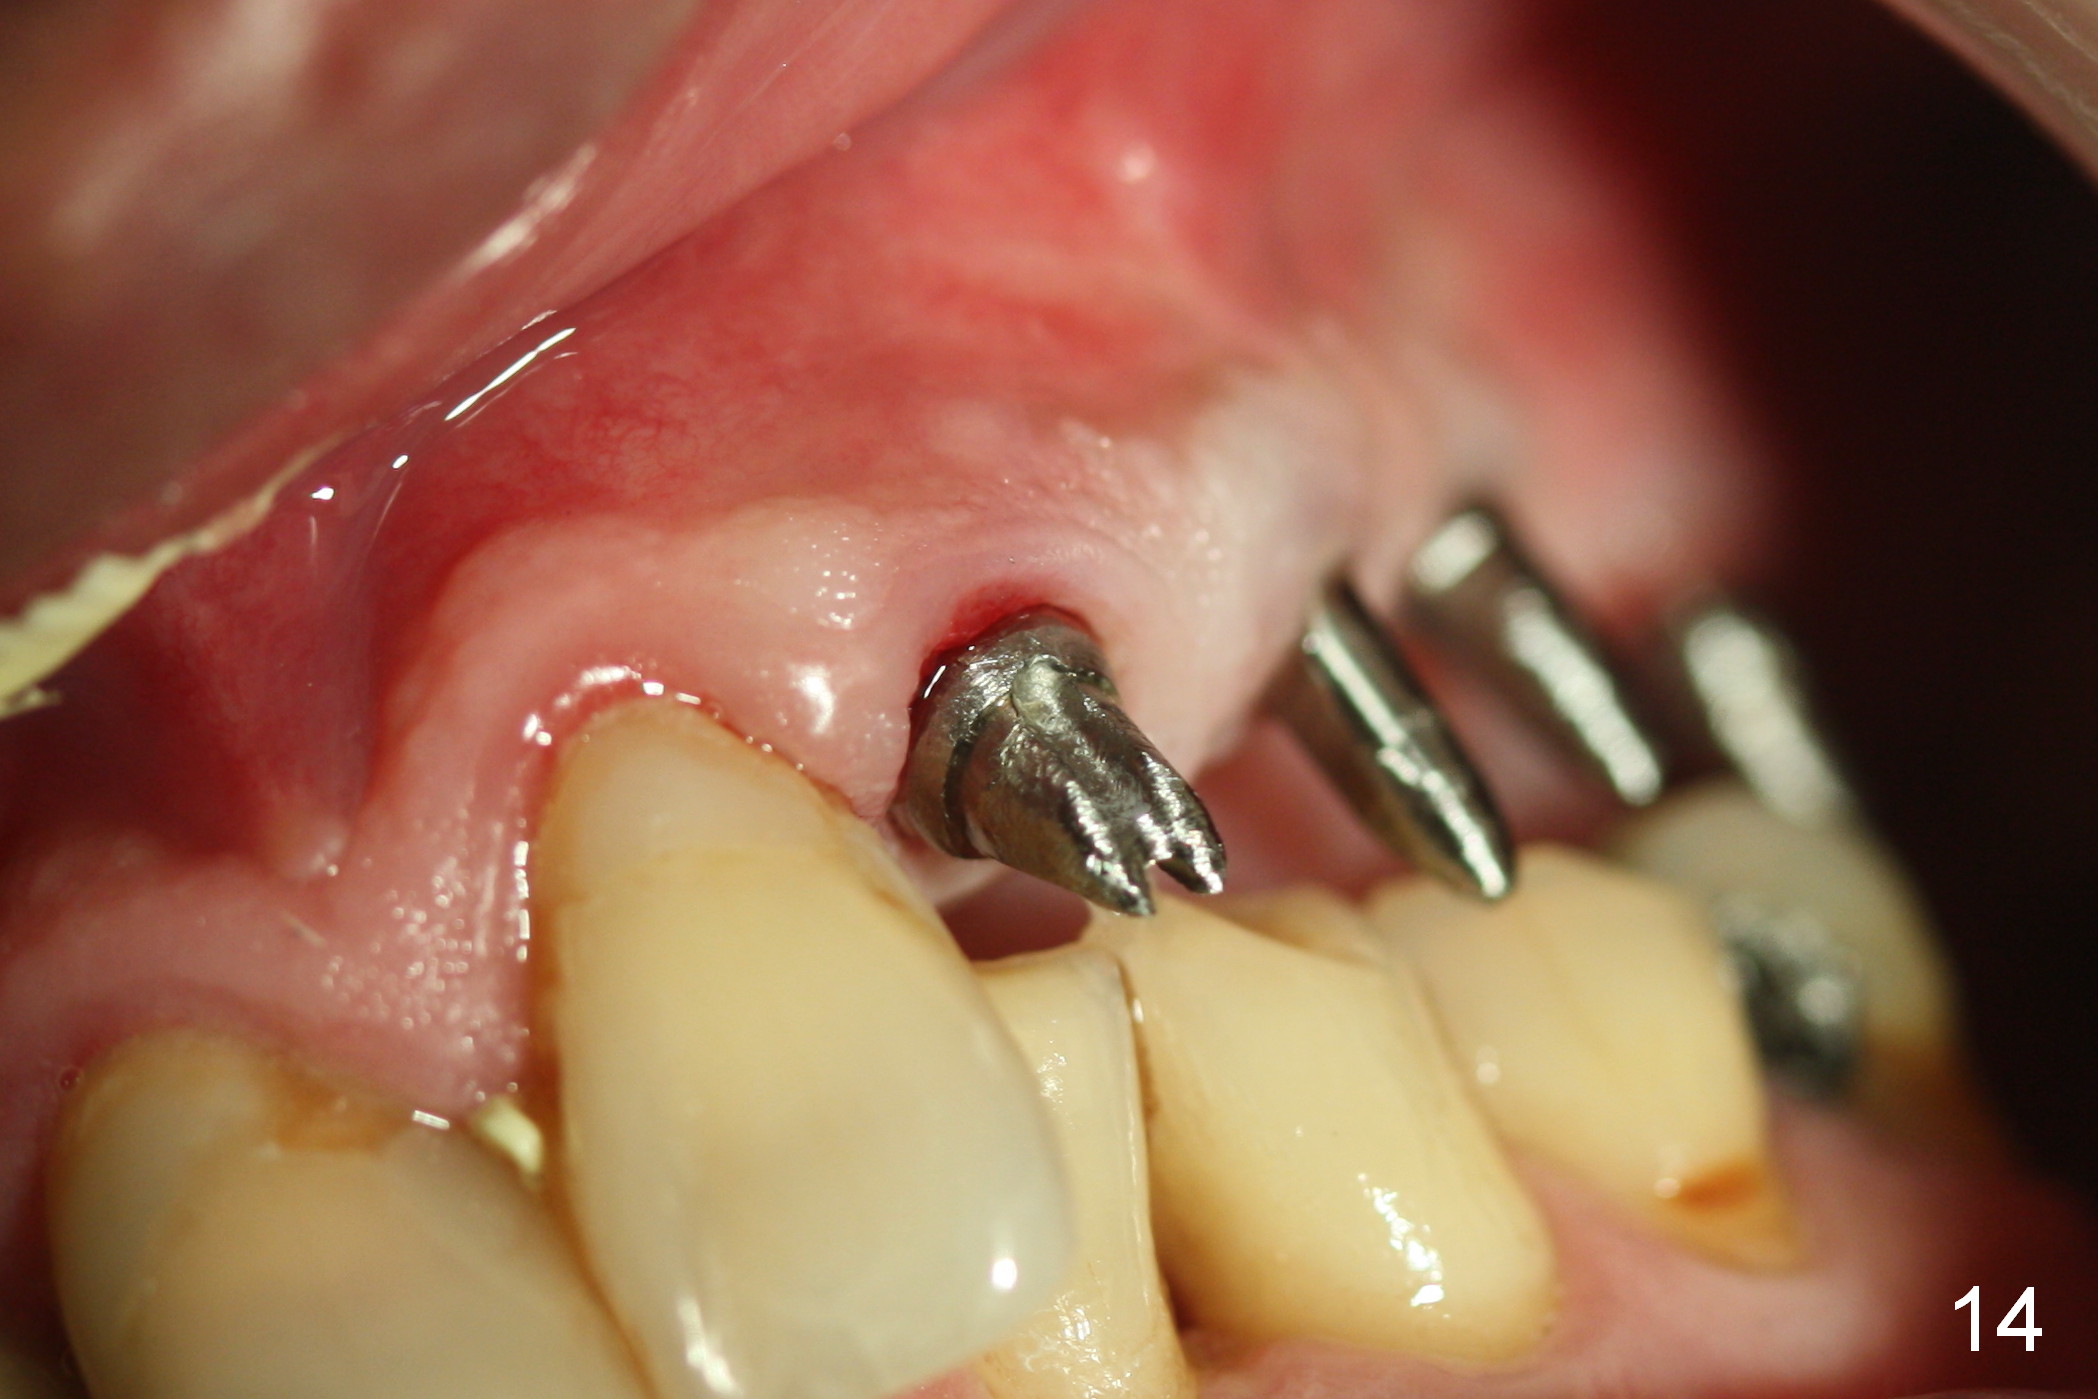

The patient returns for final restoration 3.5 months postop; it appears that the implants have osteointegrated (Fig.12,13). After reprep, there is no gross buccal plate atrophy at #10 (Fig.14).